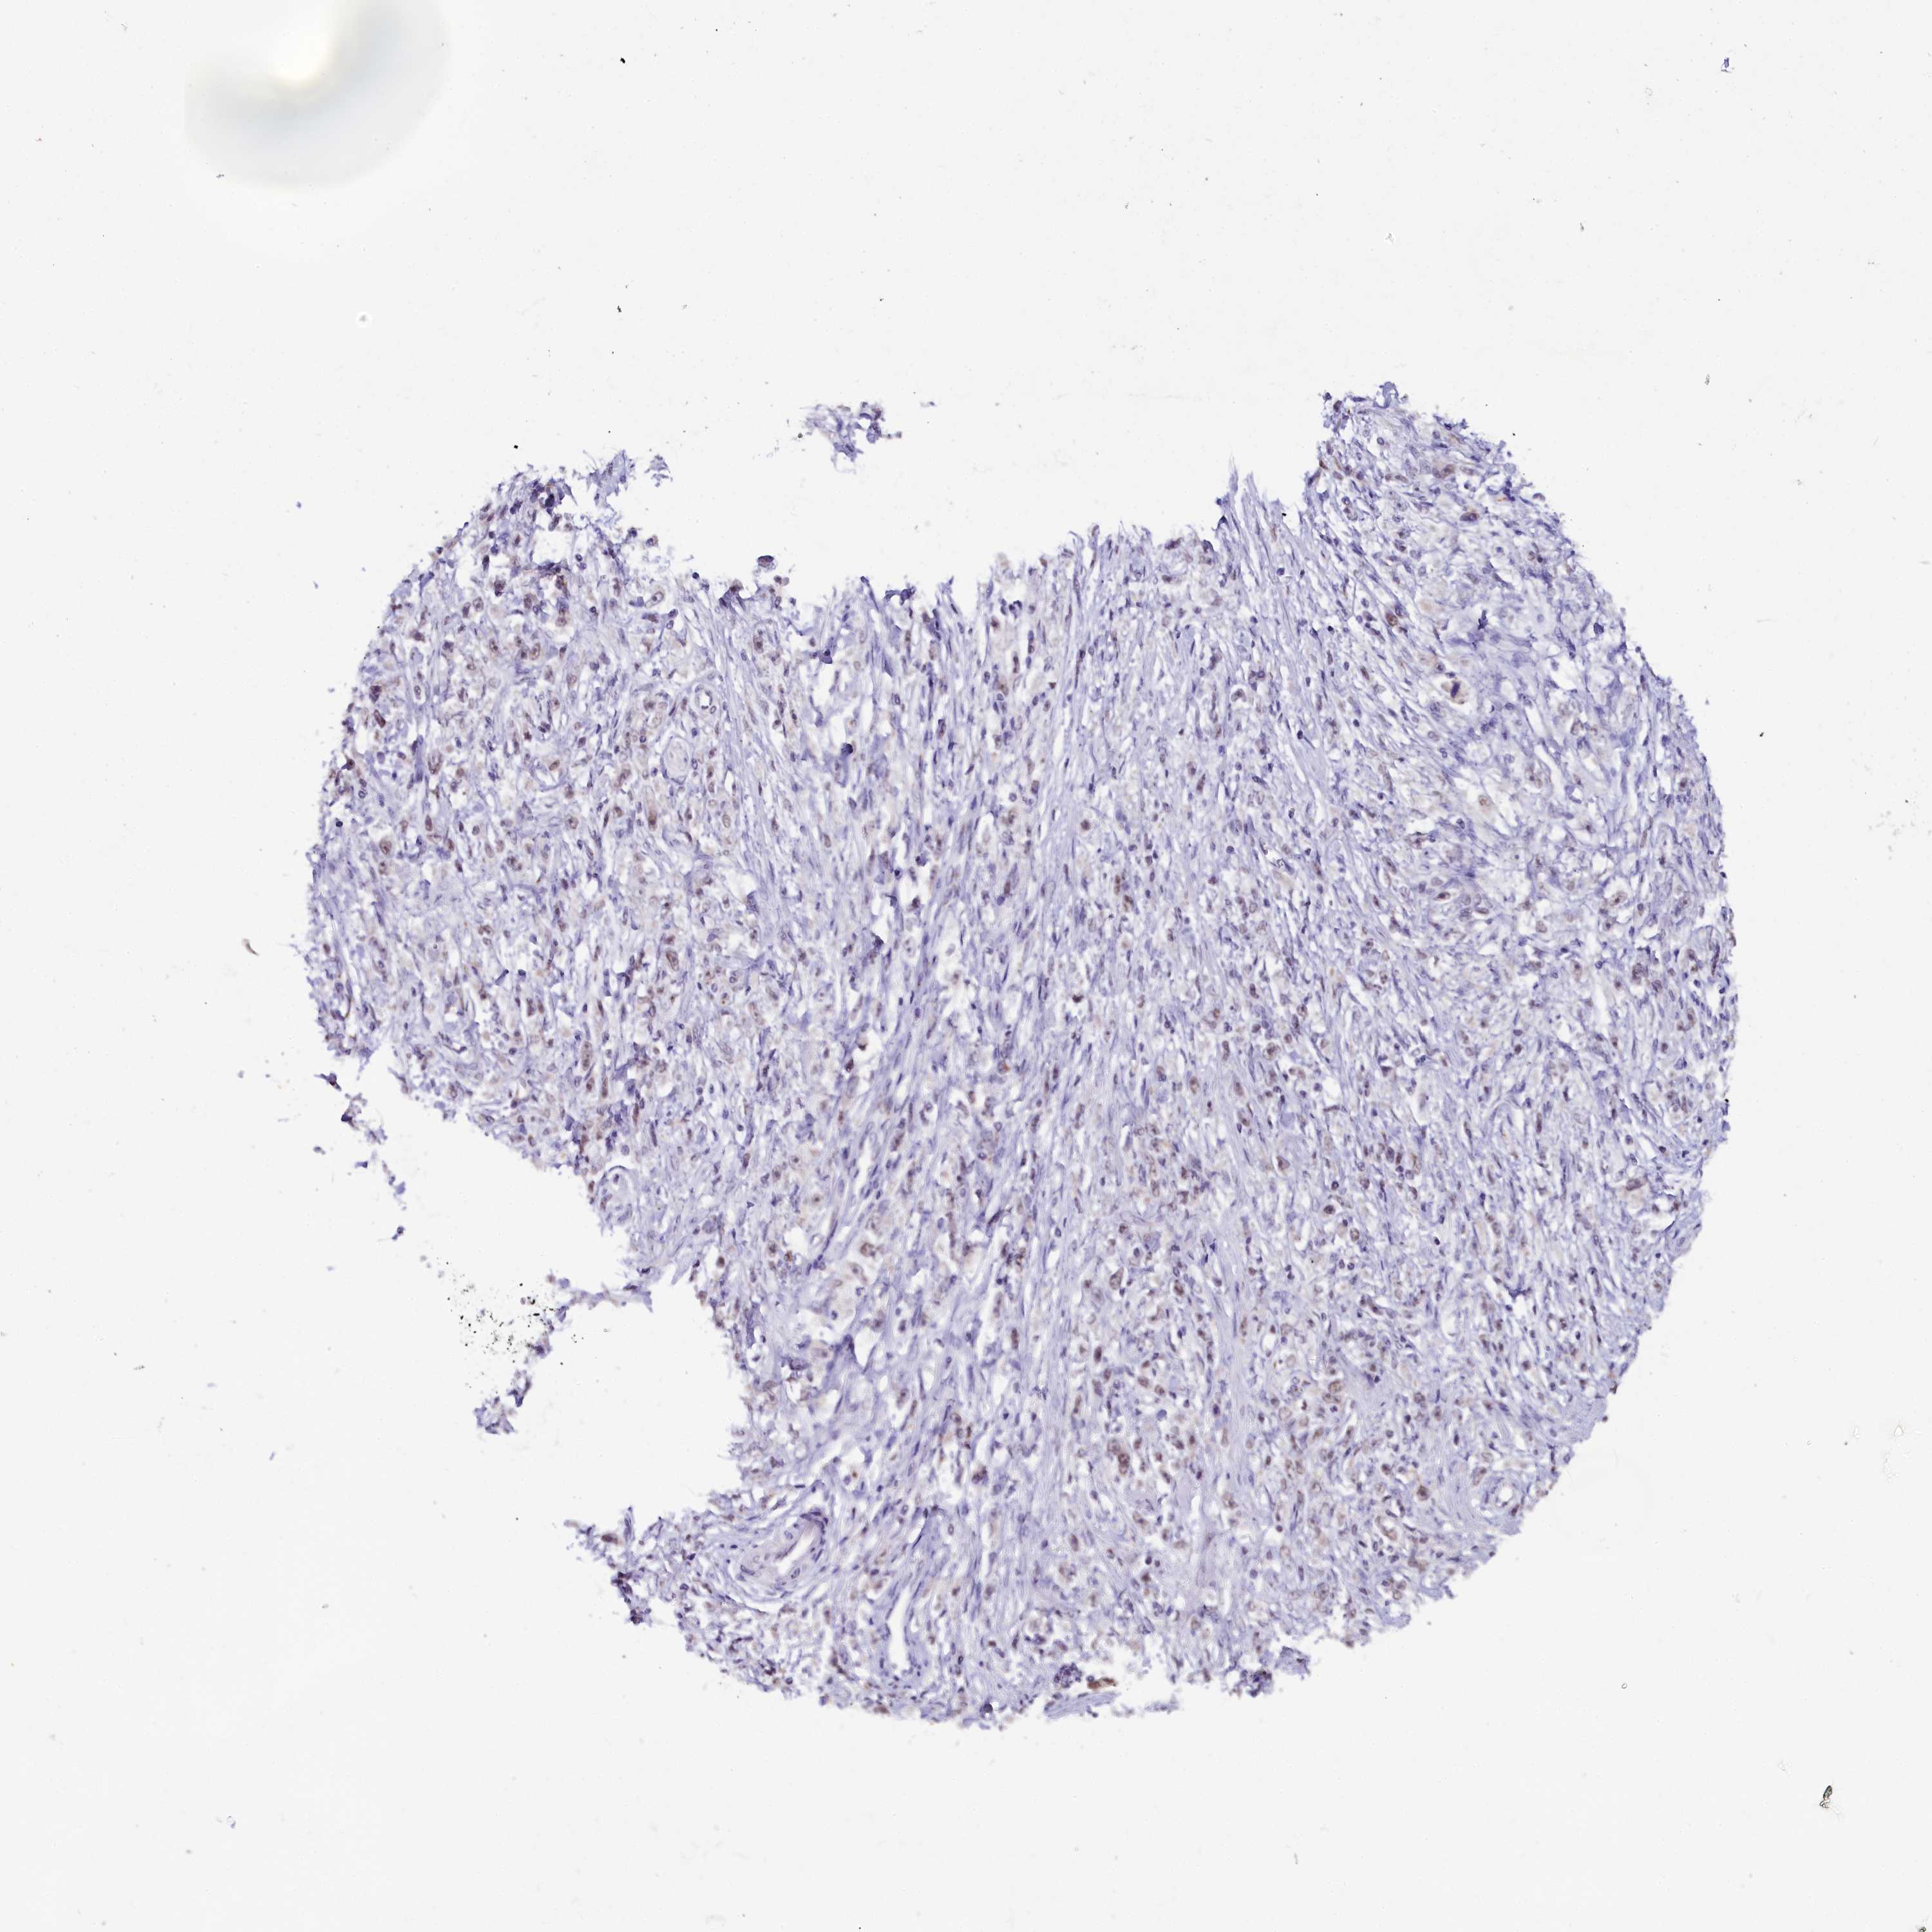

STOMACH CANCER - Protein expressioni

A mouse-over function shows sample information and annotation data. Click on an image to view it in a full screen mode. Samples can be filtered based on level of antibody staining by selecting one or several of the following categories: high, medium, low and not detected. The assay and annotation is described here.

Note that samples used for immunohistochemistry by the Human Protein Atlas do not correspond to samples in the TCGA dataset.

Antibody stainingi

Antibody staining in the annotated cell types in the current human tissue is reported as not detected, low, medium, or high, based on conventional immunohistochemistry profiling in selected tissues. This score is based on the combination of the staining intensity and fraction of stained cells.

Each image is clickable and will lead to virtual microscopy that enables deeper exploration of all samples and also displays staining intensity scores, fraction scores and subcellular localization as well as patient and tissue information for each sample.

Antibody HPA042411

Antibody HPA049031

Staining

High

Medium

Low

Not detected

Intensity

Strong

Moderate

Weak

Negative

Quantity

>75%

75%-25%

<25%

None

Location

Nuclear

Cytoplasmic/membranous

Cytoplasmic/membranous,nuclear

Adenocarcinoma, NOS